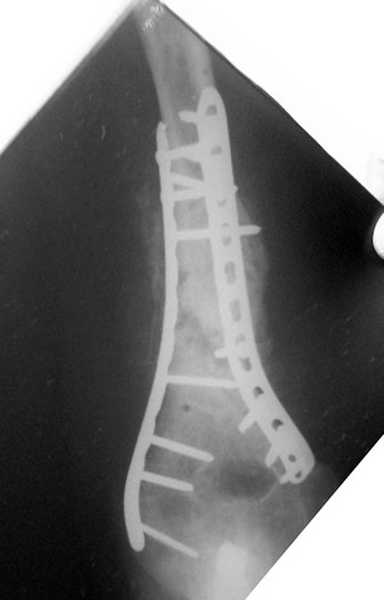

Второй случай, также после множественных операций:

пластина, аппарат, серкляж и парез нерва.

Также ревизия, из-за низкого состояния доступ был сделан через

остеотомию локтевого отростка.

Ложный сустав фиксирован двумя локинг плейт с аутокостной пластикой,

также через два месяца увидели признаки консолидации.

Движение в суставе разрешили в две недели.

Вложение не в текстовом формате было извлечено…

Имя     : 2 lat humerus.jpg

Тип     : image/jpeg

Размер  : 21591 байтов

Описание: отсутствует

Url     : http://weborto.net:8080/pipermail/ortho/attachments/20080223/b621f987/attachment-0009.jpg